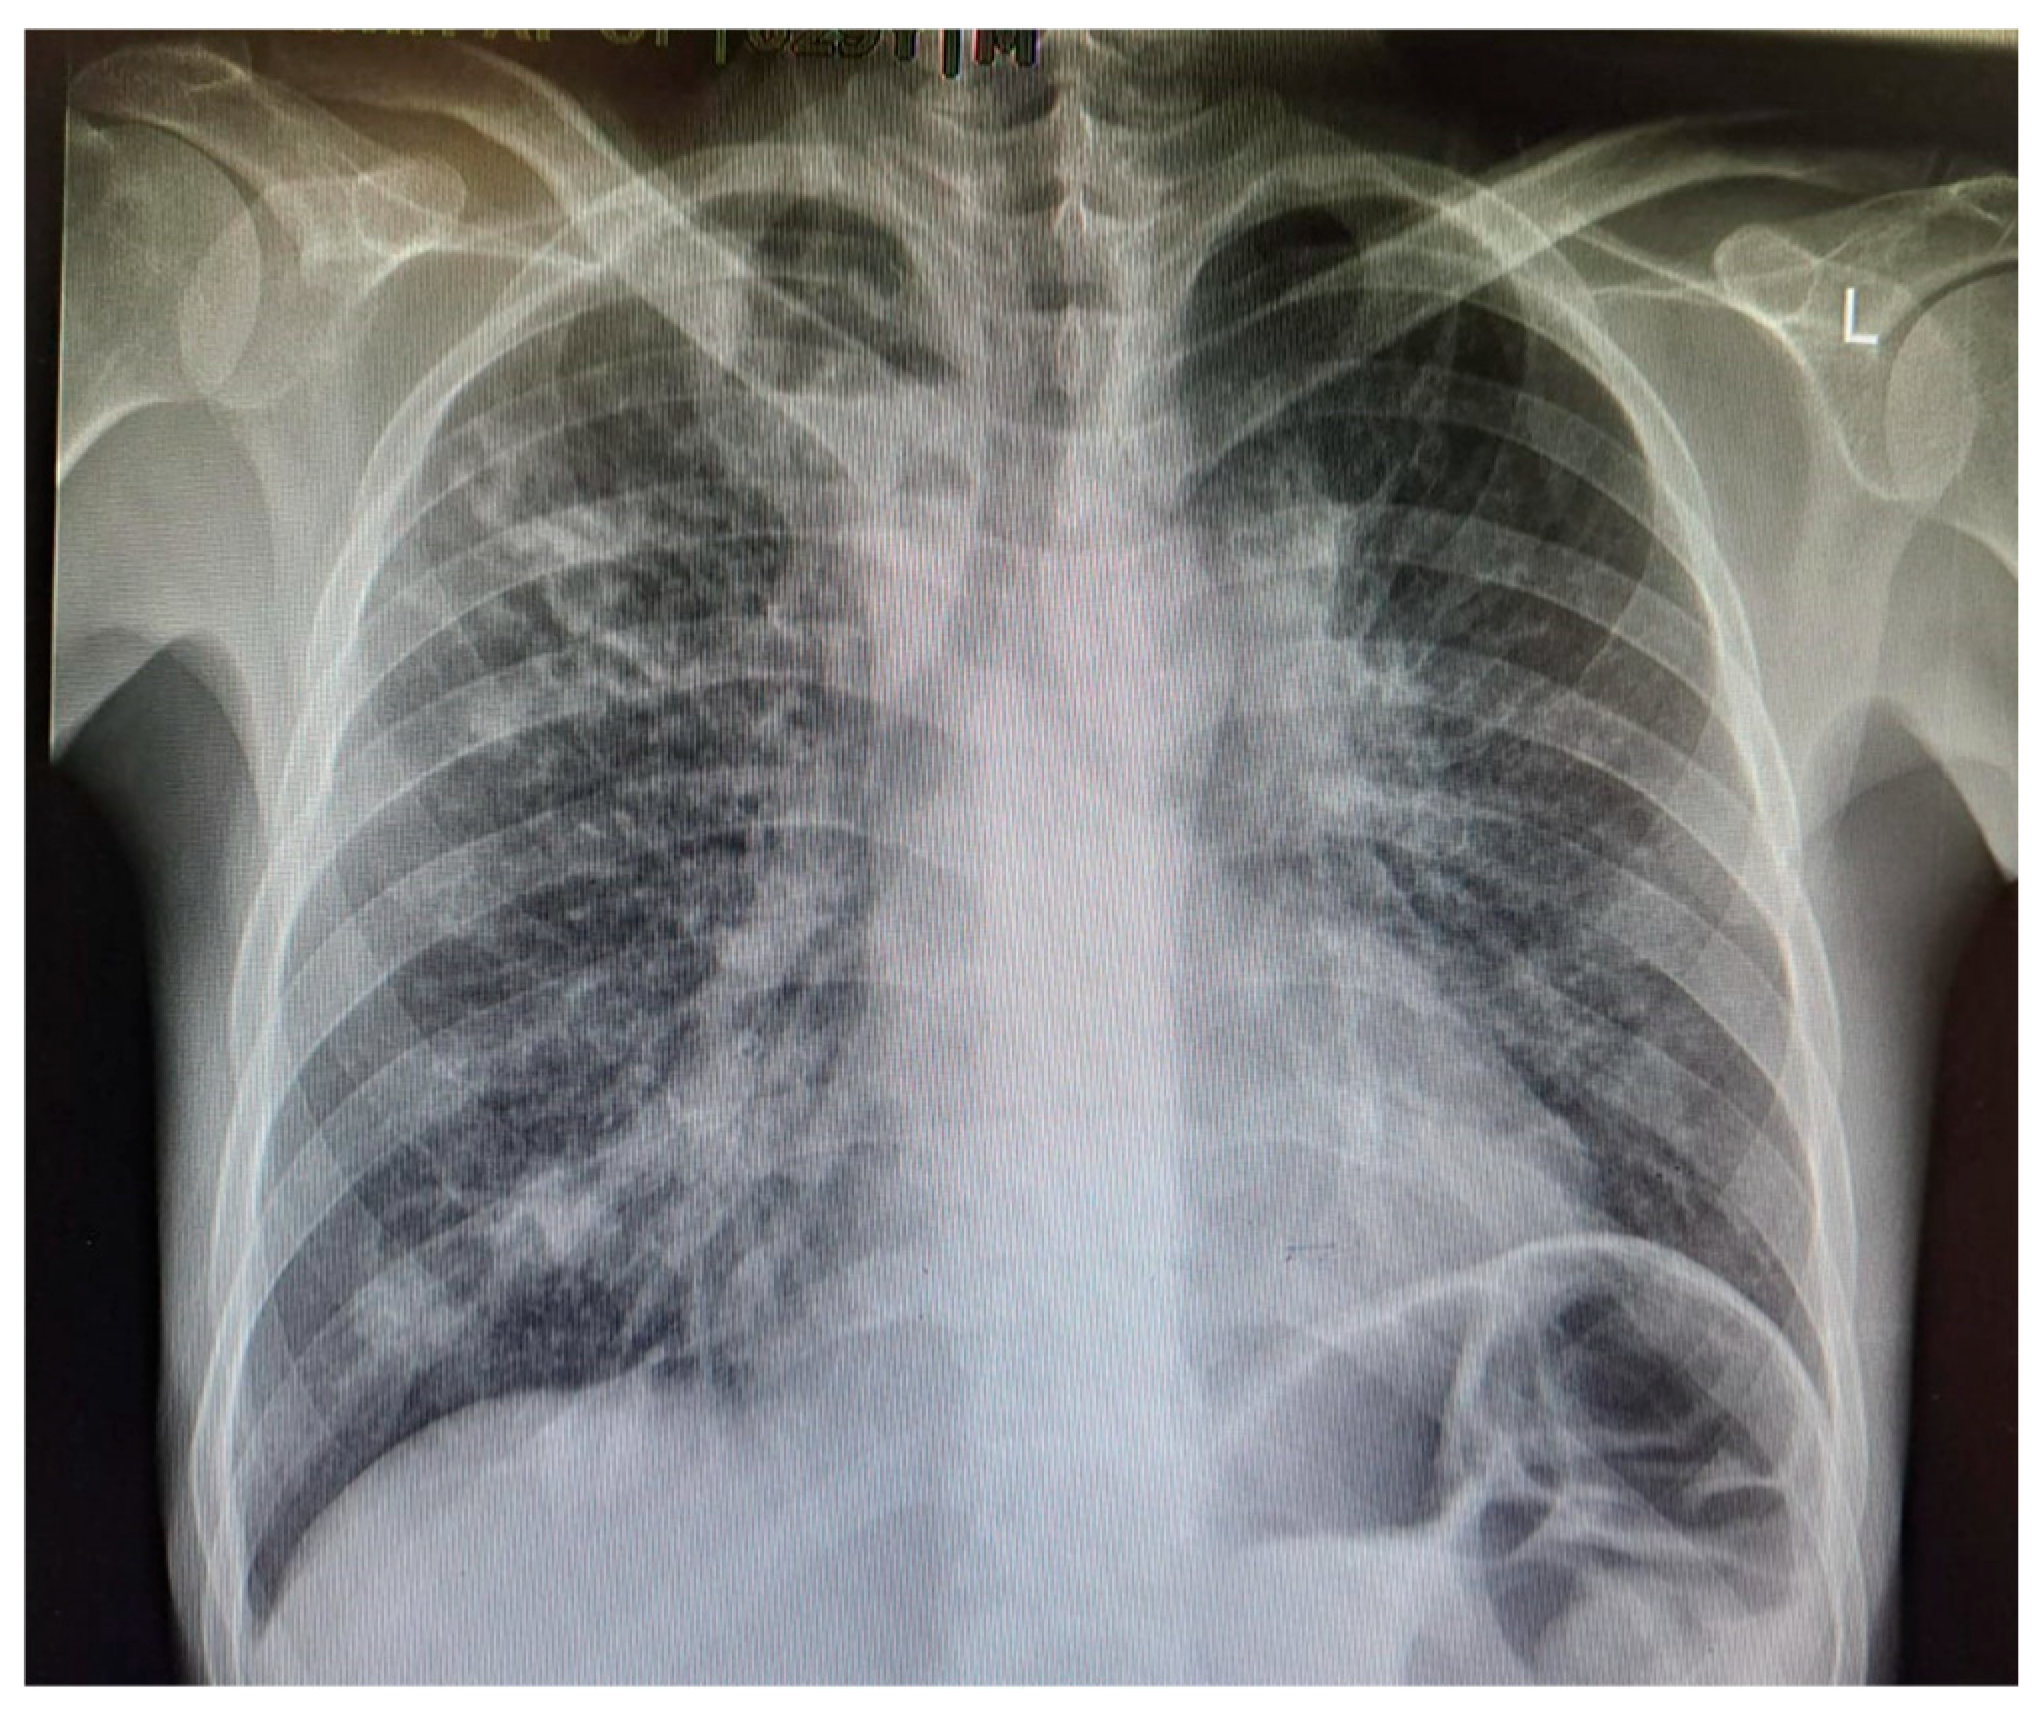

Figure 2. Chest X-ray of a 29-year-old male with active TB, showing bilateral upper lobe opacities and cavitation, consistent with advanced pulmonary TB. These findings reflect extensive lung parenchymal damage due to the infection.